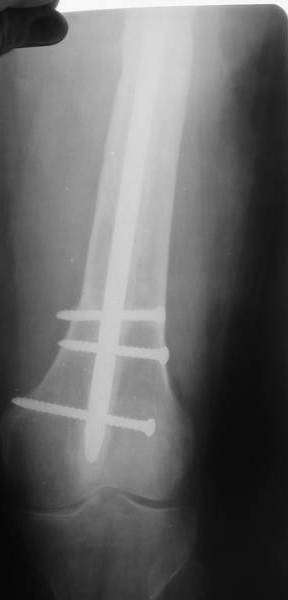

В настоящее время наш пациент ( см. http://weborto.net/forum/1177351385/index_html) ходит с одним костылем. У него периодически открывается свищ на задне-наружной поверхности бедра с умеренным серозно-гнойным отделяемым. Температура тела и анализы нормальные. На рентгенограммах имеются признаки консолидации ложного сустава.

1, 2, 3, 4 - рентгенограммы бедра от 8 августа этого года (через четыре месяца после операции);